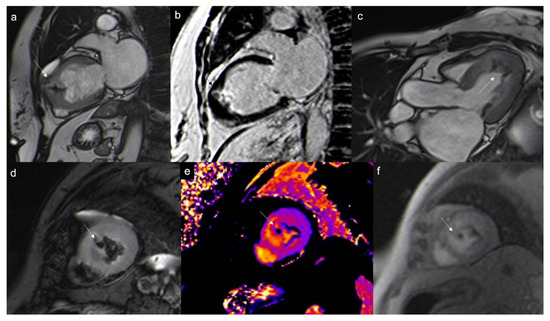

7.2.6. T1 and T2 Mapping

- Short T1/short T2 (as compared with the myocardium) for calcifications

- Short T1/long T2 for melanoma or lipomas and lipomatosis [64]

- Long T1/long T2 for most tumors, whether benign or malignant, with different degrees in particular for the T1 (close to the myocardium for rhabdomyoma, long or very long for myxomas [65] and fibroelastomas)

- T1 mapping allows for highlighting the difference between recent (<1 week) and old thrombi (>1 month), as recent thrombi have a significantly shorter T1.